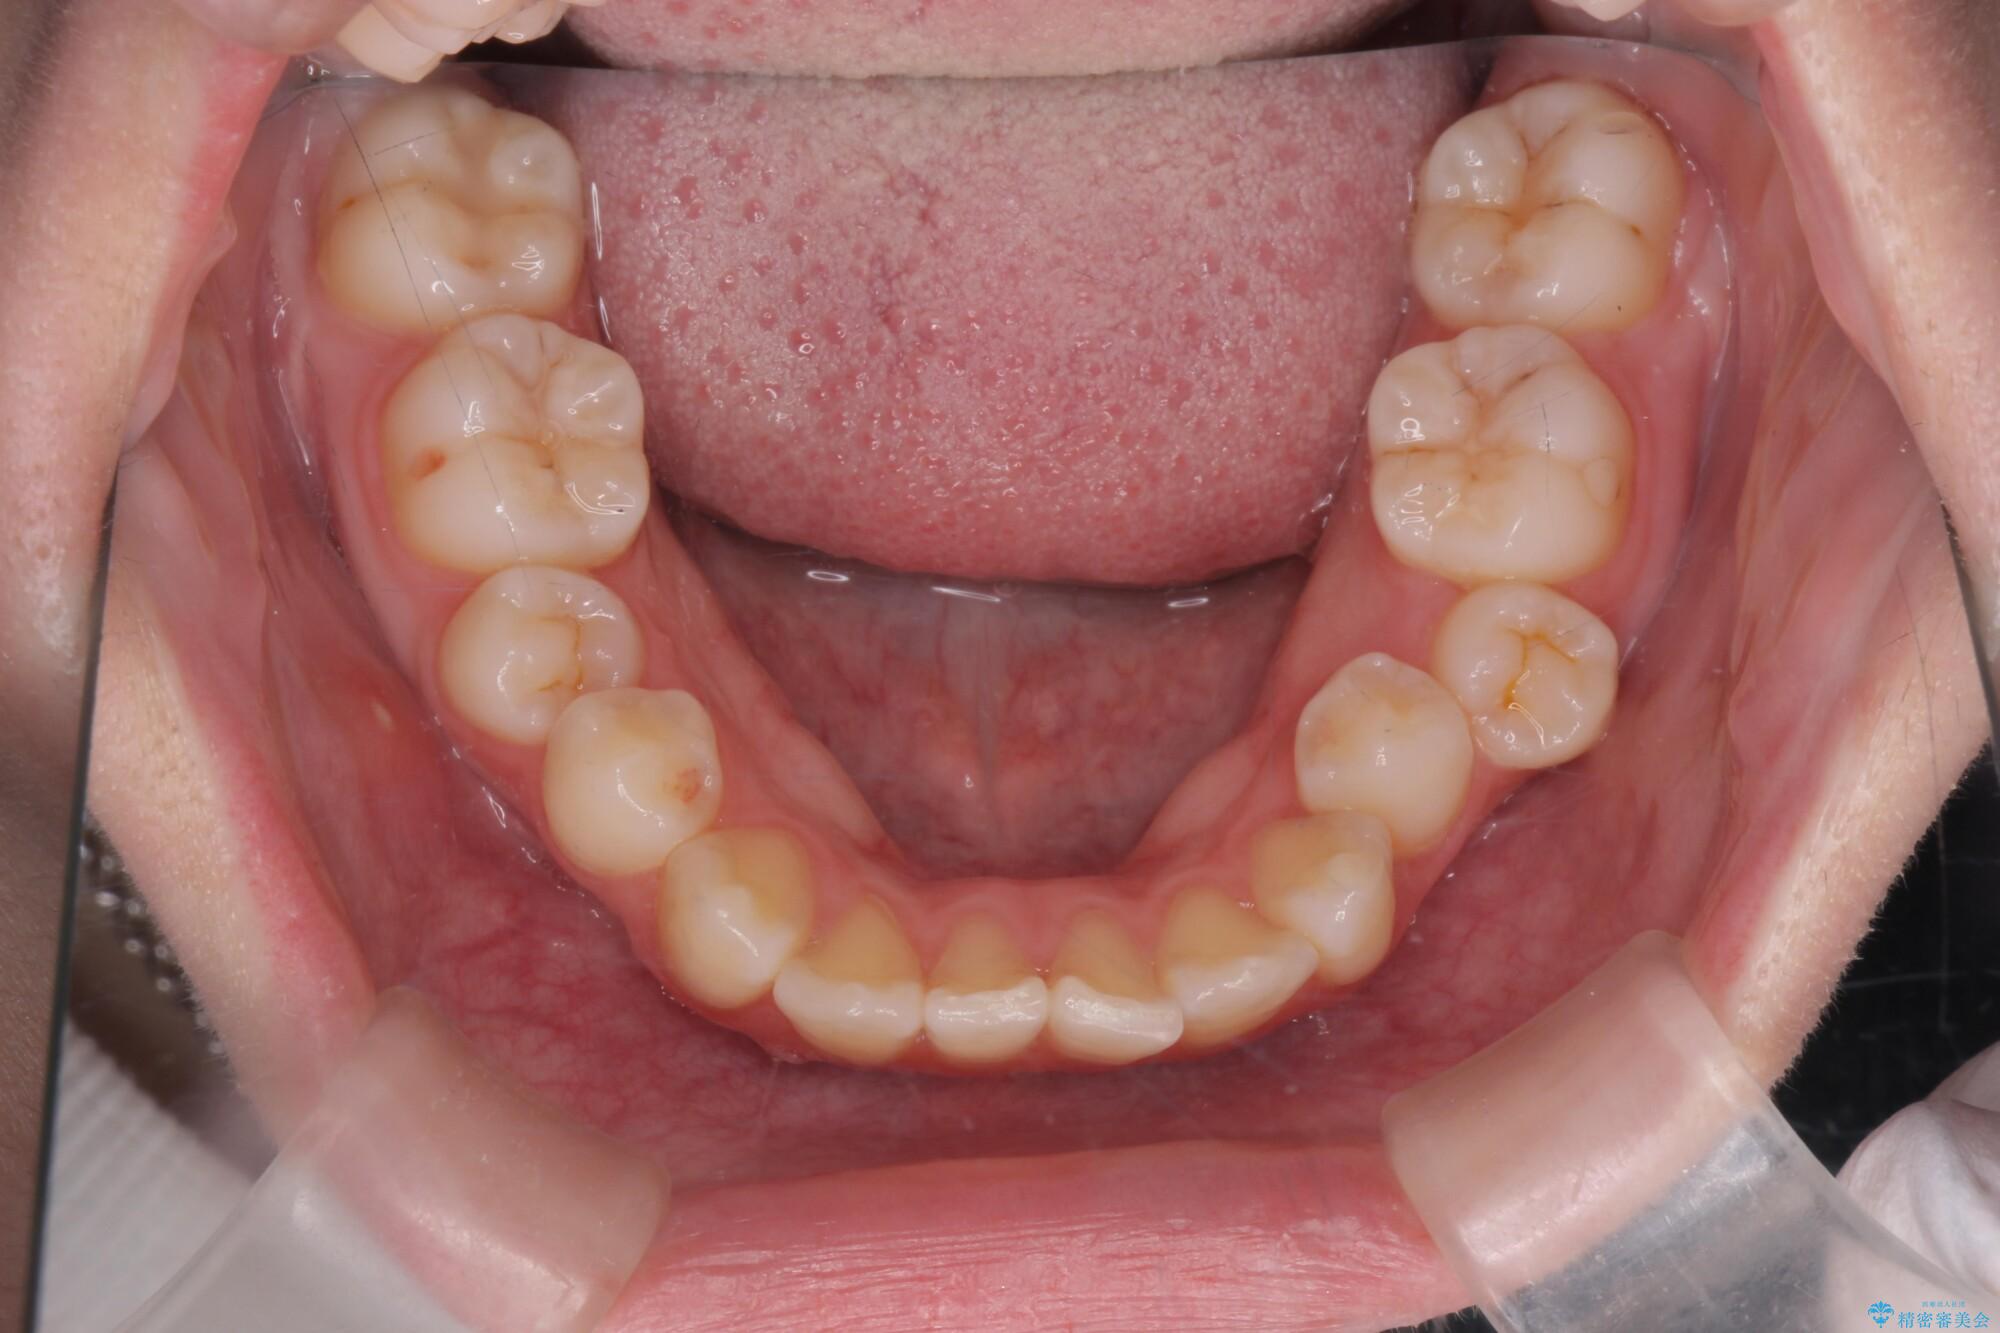

治療前

奥歯のガタつきをマウスピース矯正で改善 治療前画像 奥歯のガタつきをマウスピース矯正で改善 治療前画像 奥歯のガタつきをマウスピース矯正で改善 治療前画像

治療後

奥歯のガタつきをマウスピース矯正で改善 治療後画像 奥歯のガタつきをマウスピース矯正で改善 治療後画像 奥歯のガタつきをマウスピース矯正で改善 治療後画像